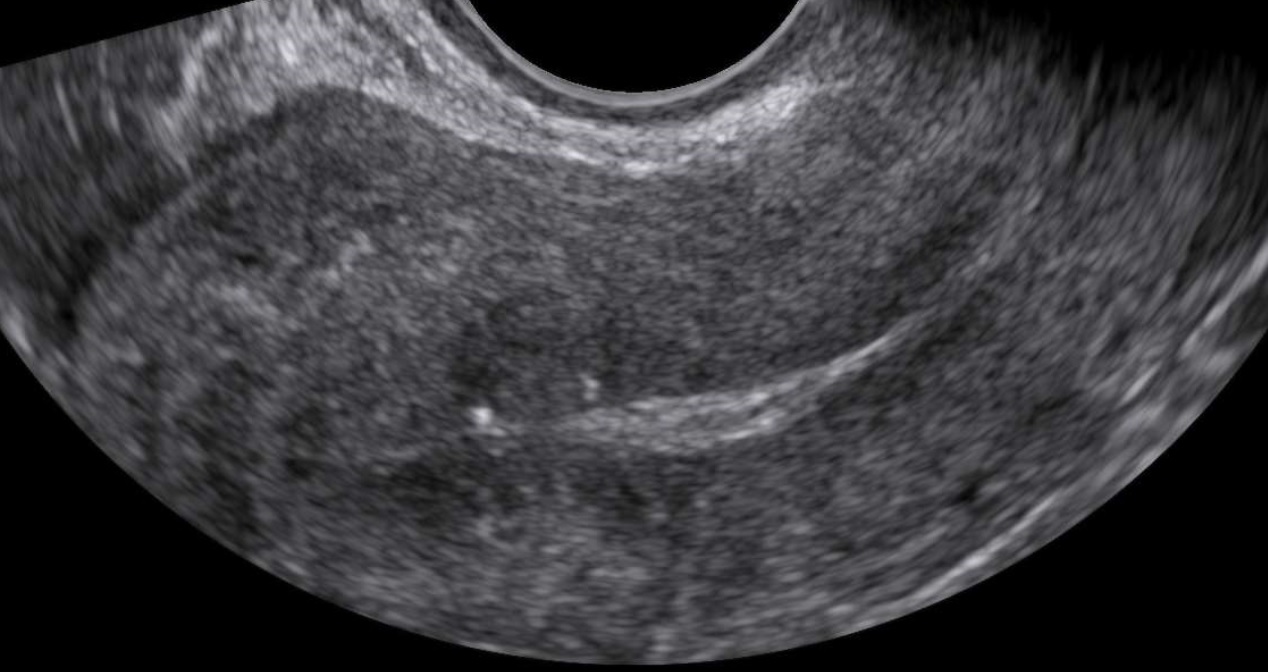

- Characteristics associated with adenomyosis according to the MUSA criteria (enlarged globular uterus, asymmetrical thickening of the myometrium, myometrial cysts, echogenic subendometrial lines and buds, hyperechogenic islands, fan shaped shadowing, an irregular or interrupted junctional zone, and translesional vascularity on color Doppler)

- Focal, diffuse, mixed-type, or adenomyoma (focal adenomyosis refers to cases where less than 25% of the myometrium of the corpus uteri is involved and more than 25% of the circumference of the lesion is surrounded by normal myometrium, estimated on that sagittal uterine section where the adenomyotic lesion appears the largest. When focal adenomyosis is distinctly demarcated and surrounded by hypertrophic myometrium, it is called an adenomyoma.)

- Myometrial layer involvement (type 1: the junctional zone, type 2: the middle myometrium, type 3: the outer myometrium – the layer between the serosa and the vascular arcade)

- Disease extent (mild: <25% of uterine volume, moderate: 25-50% or severe: >50%)